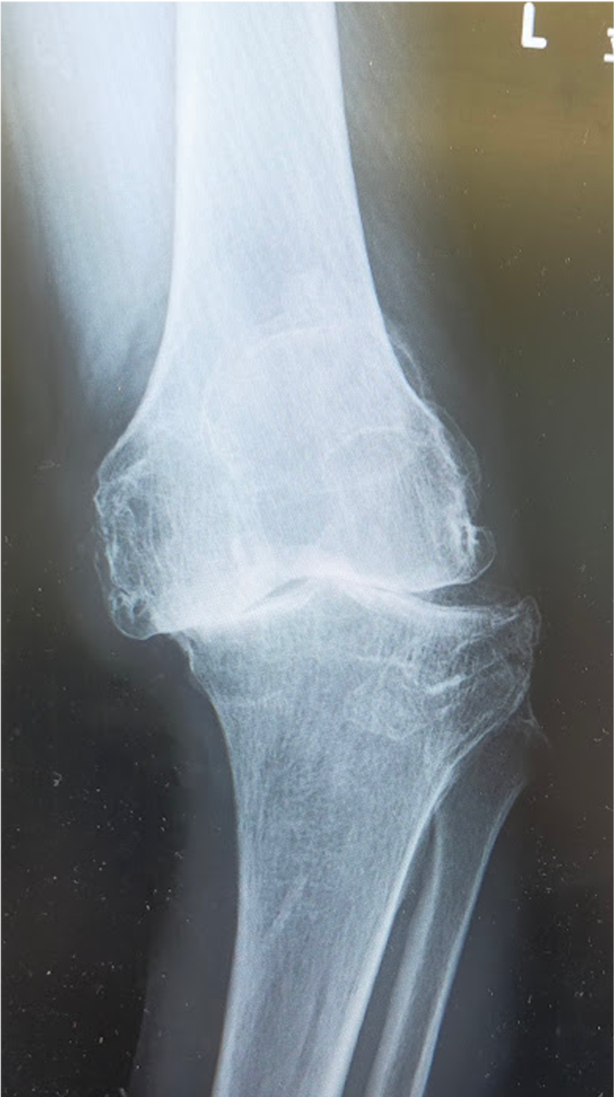

変形性膝関節症は一次性と原因疾患に続発する二次性に分類されます。わが国では年齢による退行性変化を主因とする一次性が多く、軟骨のすり減り、骨棘(骨のとげ)を伴い、多くは内反変形(O脚)を呈します。女性に多く、特に肥満との関連が強いといわれています。膝関節には歩行するだけで体重の3倍の力がかかるといわれており、病状の予防や進行を抑えるためには体重のコントロールが最も重要です。症状には波がありますが、次第に進行し、変形も悪化してきます。まずは保存加療を行いますが、痛みが強く日常生活に支障をきたすようだと、我慢するメリットはありません。痛みのない脚でより良い人生を送るために手術という選択肢もありますので、痛みで悩まれている場合は早めにご相談ください。

[手術前]

〈手術前のレントゲン〉

右ひざ